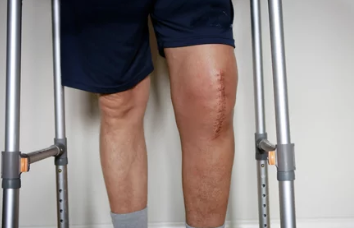

✅ 4) 수술 진행 & 지원금 지급

✔ 선정 통보 후 3개월 이내에 수술을 받아야 함

✔ 지원금은 병원으로 직접 지급되며, 환자는 본인 부담금만 지불하면 됨